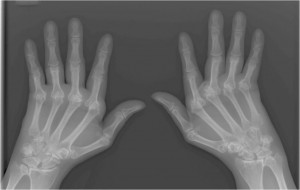

Majority of the world’s population suffer from rheumatoid arthritis. As a result pain in the joints is a common symptom. But are you aware that depression is a major concern amongst the patients suffering from this ailment? The higher the pain, the higher the rate of depression in the patient. A lot of research has been done in this field. As per the research and their findings nearly 13 to 20% of the patients suffer from depression. This percentage is highly dependent on the social demographics as well as the characteristics of the ailment. Thus the patients have a double chance of suffering from depression compared to the general public. There is another thing that we need to consider here. The way a patient deals with depression has a lot to do with how they deal with their pain and their level of interaction with their practitioner.